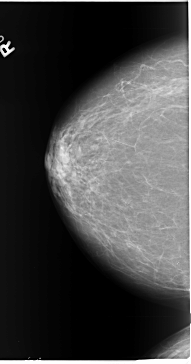

B_3089_1.RIGHT_CC

RIGHT_CC LINES 5816 PIXELS_PER_LINE 3048 BITS_PER_PIXEL 12 RESOLUTION 50 NON_OVERLAY